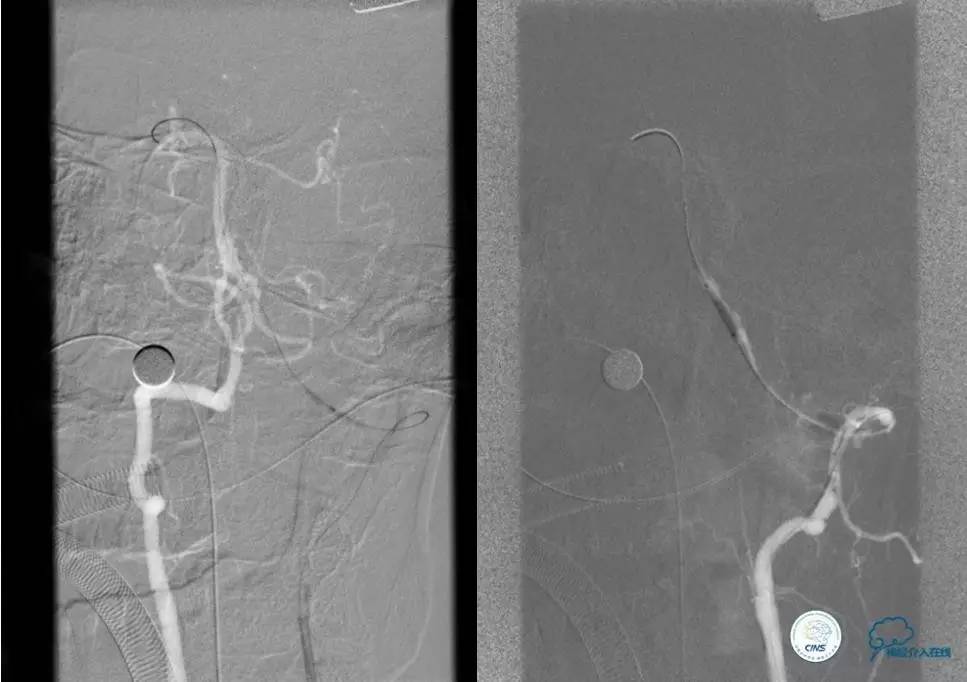

术前DSA

▼2013-12-13

▼2013-12-27

术后仍残余部分狭窄,但头晕明显缓解。

术后3个月复查时予行支架内球囊扩张,狭窄改善。